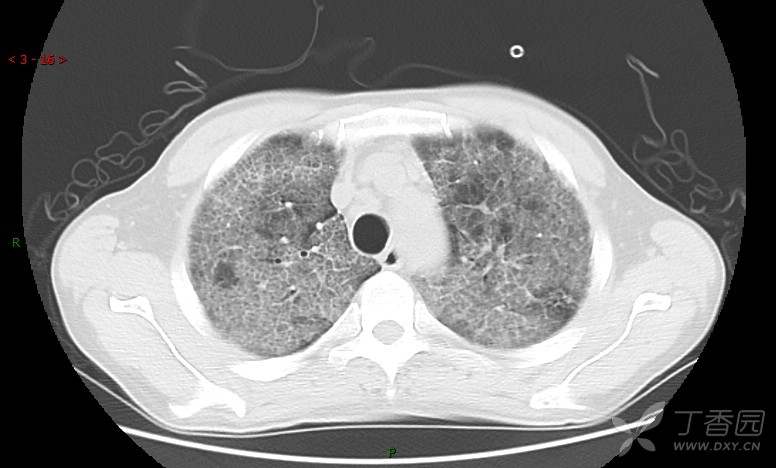

地图+铺路石征=PAP?那升高的CEA怎么说(病例3连发,附其他2例链接)

患者男,42岁,咳嗽半年余,加重伴憋喘2月余。

血清肿瘤相关抗原116.22U/ml↑(0--95);

癌胚抗原 61.96 ng/mL ↑ 0--5

神经特异性烯醇化酶 33.12 ng/ml ↑ 0--16.3

细胞角蛋白19片段测定 40.23 ng/ml ↑ ≤3.3

肺内弥漫性网状结节影,PET-CT却无阳性病灶,这是?(附其他2例链接)